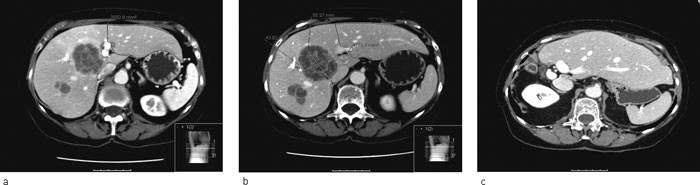

Ved CT-kontroll median 41 dager (13 – 67 dager) etter vellykket portveneembolisering var veksten av leverresten median 45 % (9 – 100 %). Forholdet mellom gjenværende lever og totalt levervolum økte fra median 0,17 (0,09 – 0,31) til median 0,25 (0,16 – 0,46) etter emboliseringen (fig 3).

Av de ti pasientene som fikk utført leverreseksjon hadde ni metastaser etter kolorektalcancer og én metastaser fra nevroendokrin pancreascancer. To fikk intervensjonstrengende komplikasjoner. Begge hadde gallelekkasje som ble behandlet med endoskopisk innlagt stent i galleveier og perkutant eksternt dren. Mediant tumorantall var fire (1 – 14 tumorer) og median tumorstørrelse 5 centimeter (4 – 11 cm). Fri reseksjonsrand ble påvist hos sju pasienter. Mikroskopisk ikke-fri reseksjonsrand ble påvist hos tre pasienter. Figur 4 viser CT-undersøkelse før og etter portveneembolisering samt etter leverreseksjon.